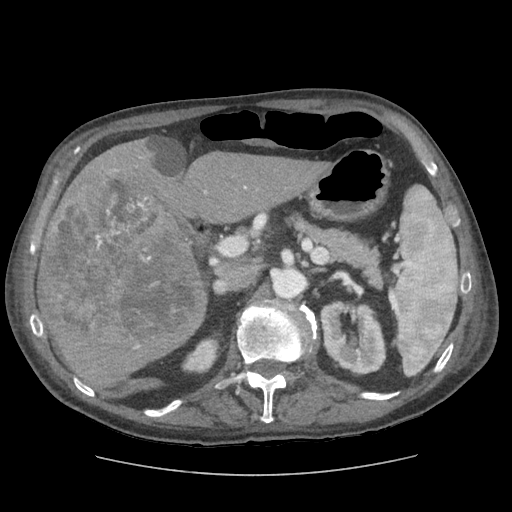

79 M with PMH of CKD, HLD, prostate cancer s/p prostatectomy + radiation presenting with feelings of fogginess, upset stomach, and diarrhea. Originally worked up at OSH, imaging concerning for a hepatic mass.

148/77 mmHg / 95 bpm / 15 breaths/min / 98.1°F / 98 ORA

sclera anicteric, no jaundice

AST 112, ALT 34, Alk Phos 202, CEA 2, CA 19-9 4